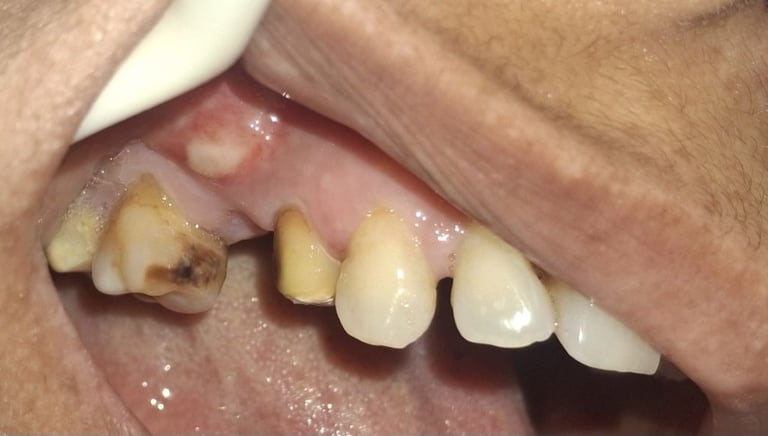

When Is Tooth Extraction Needed?

Tooth extraction may be recommended in cases of:

Severe tooth decay or infection

Broken or fractured tooth beyond repair

Advanced gum disease

All images shown here represent real clinical cases of teeth extractions done at our dental clinic with patient consent.

Illustrative images and similar real clinical cases requiring tooth extraction